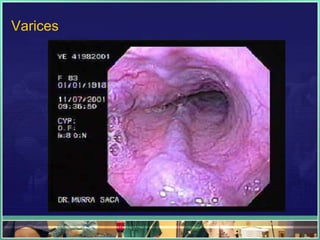

Varices

– Esophagogastric varices with or without portal

hypertensive gastropathy (10%)